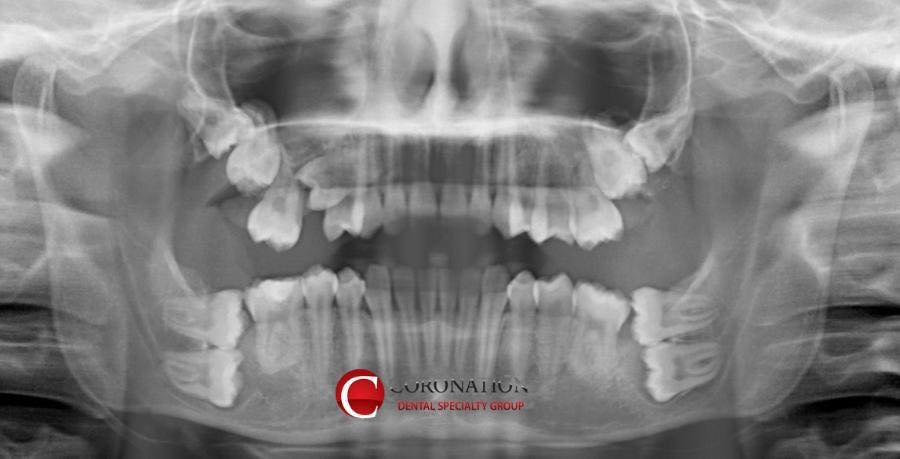

| Subject | [약혐]치과에서 보면 소름 돋을 엑스레이 사진 |

둘 다 엄청 힘든 케이스인가봐요.... 윗 사진은 어금니가 엄청 많이 있는 케이스, 아래 사진은 작은 치아종양(?)같은게 어금니 대신 그 자리를 메우고 있는 ㅠㅠ 다 제거하고 임플란트 해야하나봐요 0